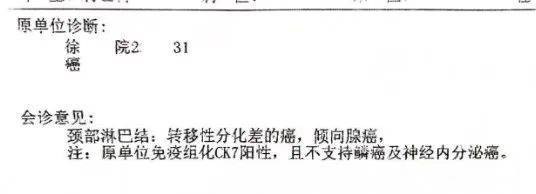

经淋巴转移灶穿刺活检,符合转移性非小细胞肺癌,大细胞肺癌不能排除,后经省医院病理会诊,会诊意见:倾向腺癌,且不支持鳞癌及神经内分泌癌,免疫组化结果 tps 约2%。

图片来源:患者提供